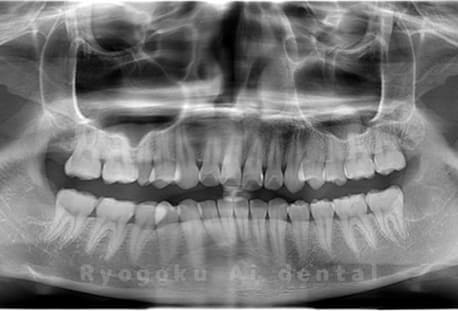

Case15

- 下顎左右2本の親知らず

- 治療内容

- 下顎左右2本の親知らずを抜歯したケースです。

<リスク・副作用>

手術後は痛み、腫れ、痺れなどの副作用が生じる場合があります。